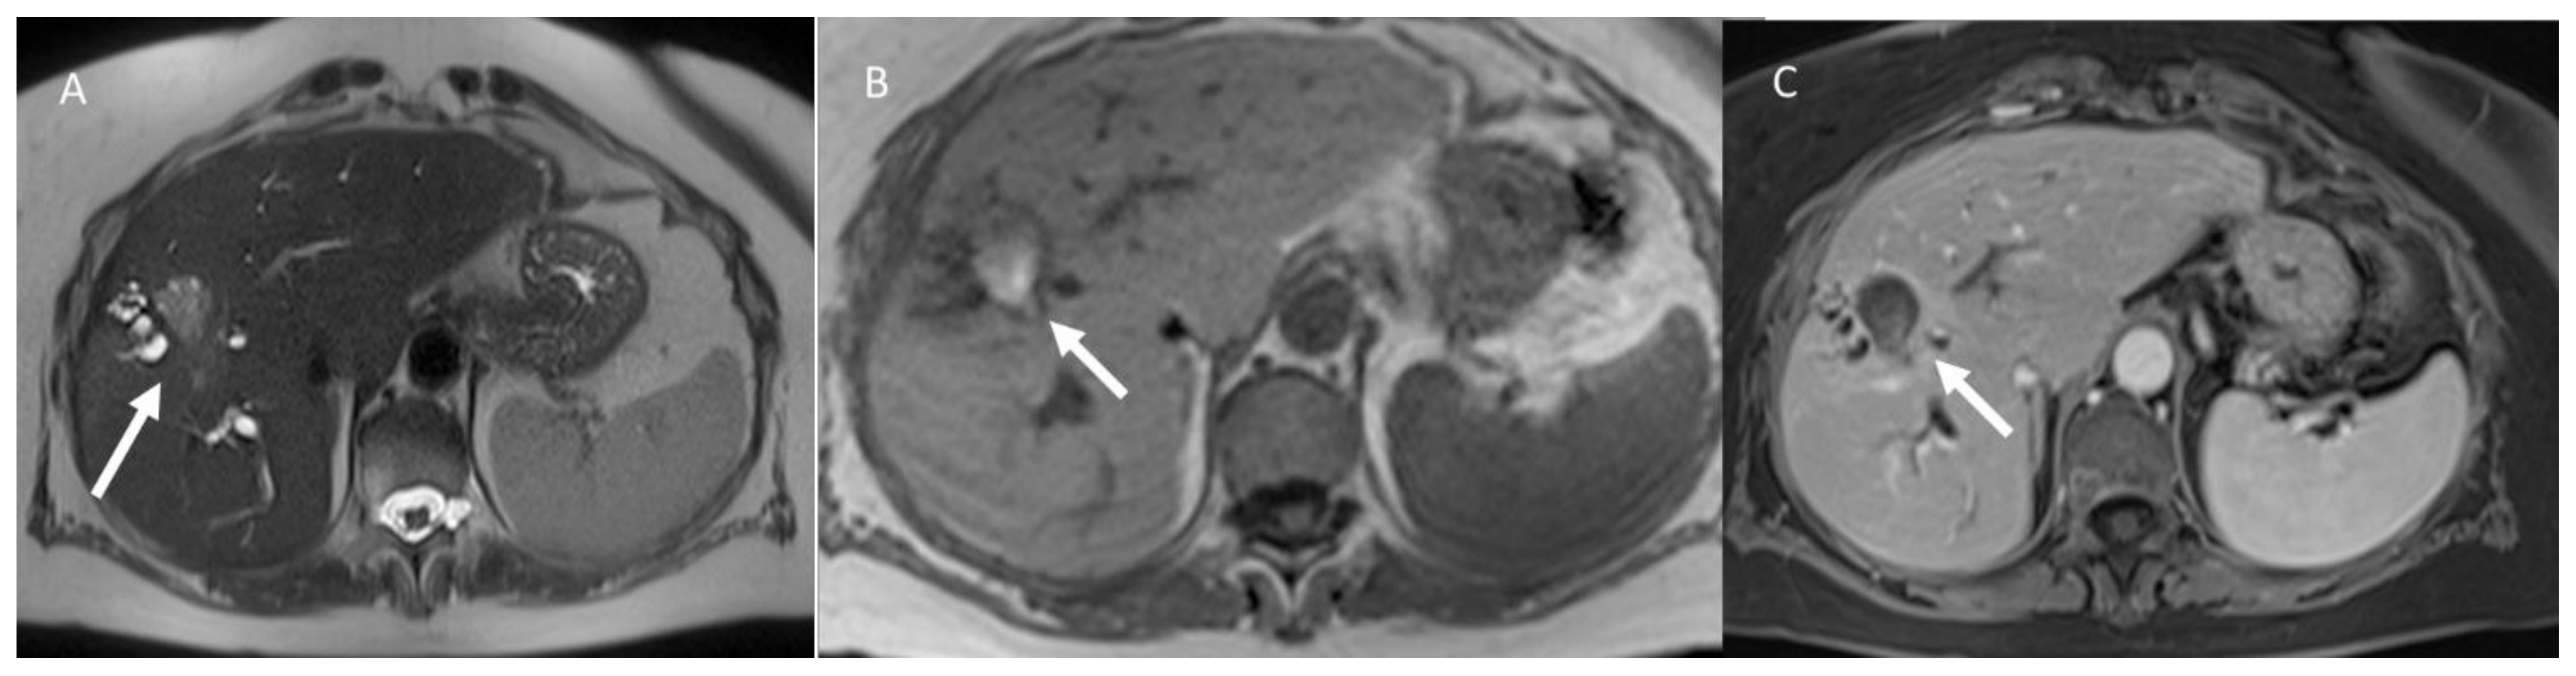

- Granata, V.; Grassi, R.; Fusco, R.; Belli, A.; Cutolo, C.; Pradella, S.; Grazzini, G.; La Porta, M.; Brunese, M.C.; De Muzio, F.; et al. Diagnostic evaluation and ablation treatments assessment in hepatocellular carcinoma. Infect. Agents Cancer 2021, 16, 53. [Google Scholar] [CrossRef] [PubMed]

- Granata, V.; Grassi, R.; Fusco, R.; Setola, S.; Belli, A.; Piccirillo, M.; Pradella, S.; Giordano, M.; Cappabianca, S.; Brunese, L.; et al. Abbreviated MRI Protocol for the Assessment of Ablated Area in HCC Patients. Int. J. Environ. Res. Public Health 2021, 18, 3598. [Google Scholar] [CrossRef]